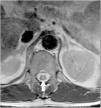

Presentamos el caso de un varón de 63 años con cirrosis hepática mixta (alcohólica y por virus de la hepatitis C) y diagnóstico de hepatocarcinoma de 14mm en segmento III y de 40mm en el segmento VI. Se realizó quimioembolización transarterial (QETA) de hepatocarcinoma mediante cateterización supraselectiva de las arterias nutricias de los nódulos tumorales y se embolizaron con doxorrubicina (DC-Beads 100-300 μ y 300-500μ) (fig. 1). Tras el procedimiento, apareció clínica compatible con retención urinaria, parestesias y paresia en ambos miembros inferiores con imposibilidad para deambular. En la resonancia magnética dorsolumbar urgente por sospecha de isquemia medular tras QETA se observó incremento de señal de la porción distal del cordón y del cono medular con moderada restricción en la secuencia de difusión (figs. 2-4), en posible relación con lesión isquémica aguda a nivel de T11, que la confirmó. Tras la rehabilitación, fue dado de alta con deambulación conservada.

La QETA tiene su base en la vascularización casi exclusivamente arterial que tiene el hepatocarcinoma1. En nuestro paciente es posible que el cuadro clínico presentado se explique por la existencia de una arteria nutricia del tumor como colateral de una de las arterias espinales que irrigan a la médula, pasando así el material quimioterápico a la médula espinal y provocando inusual isquemia medular aguda transitoria.